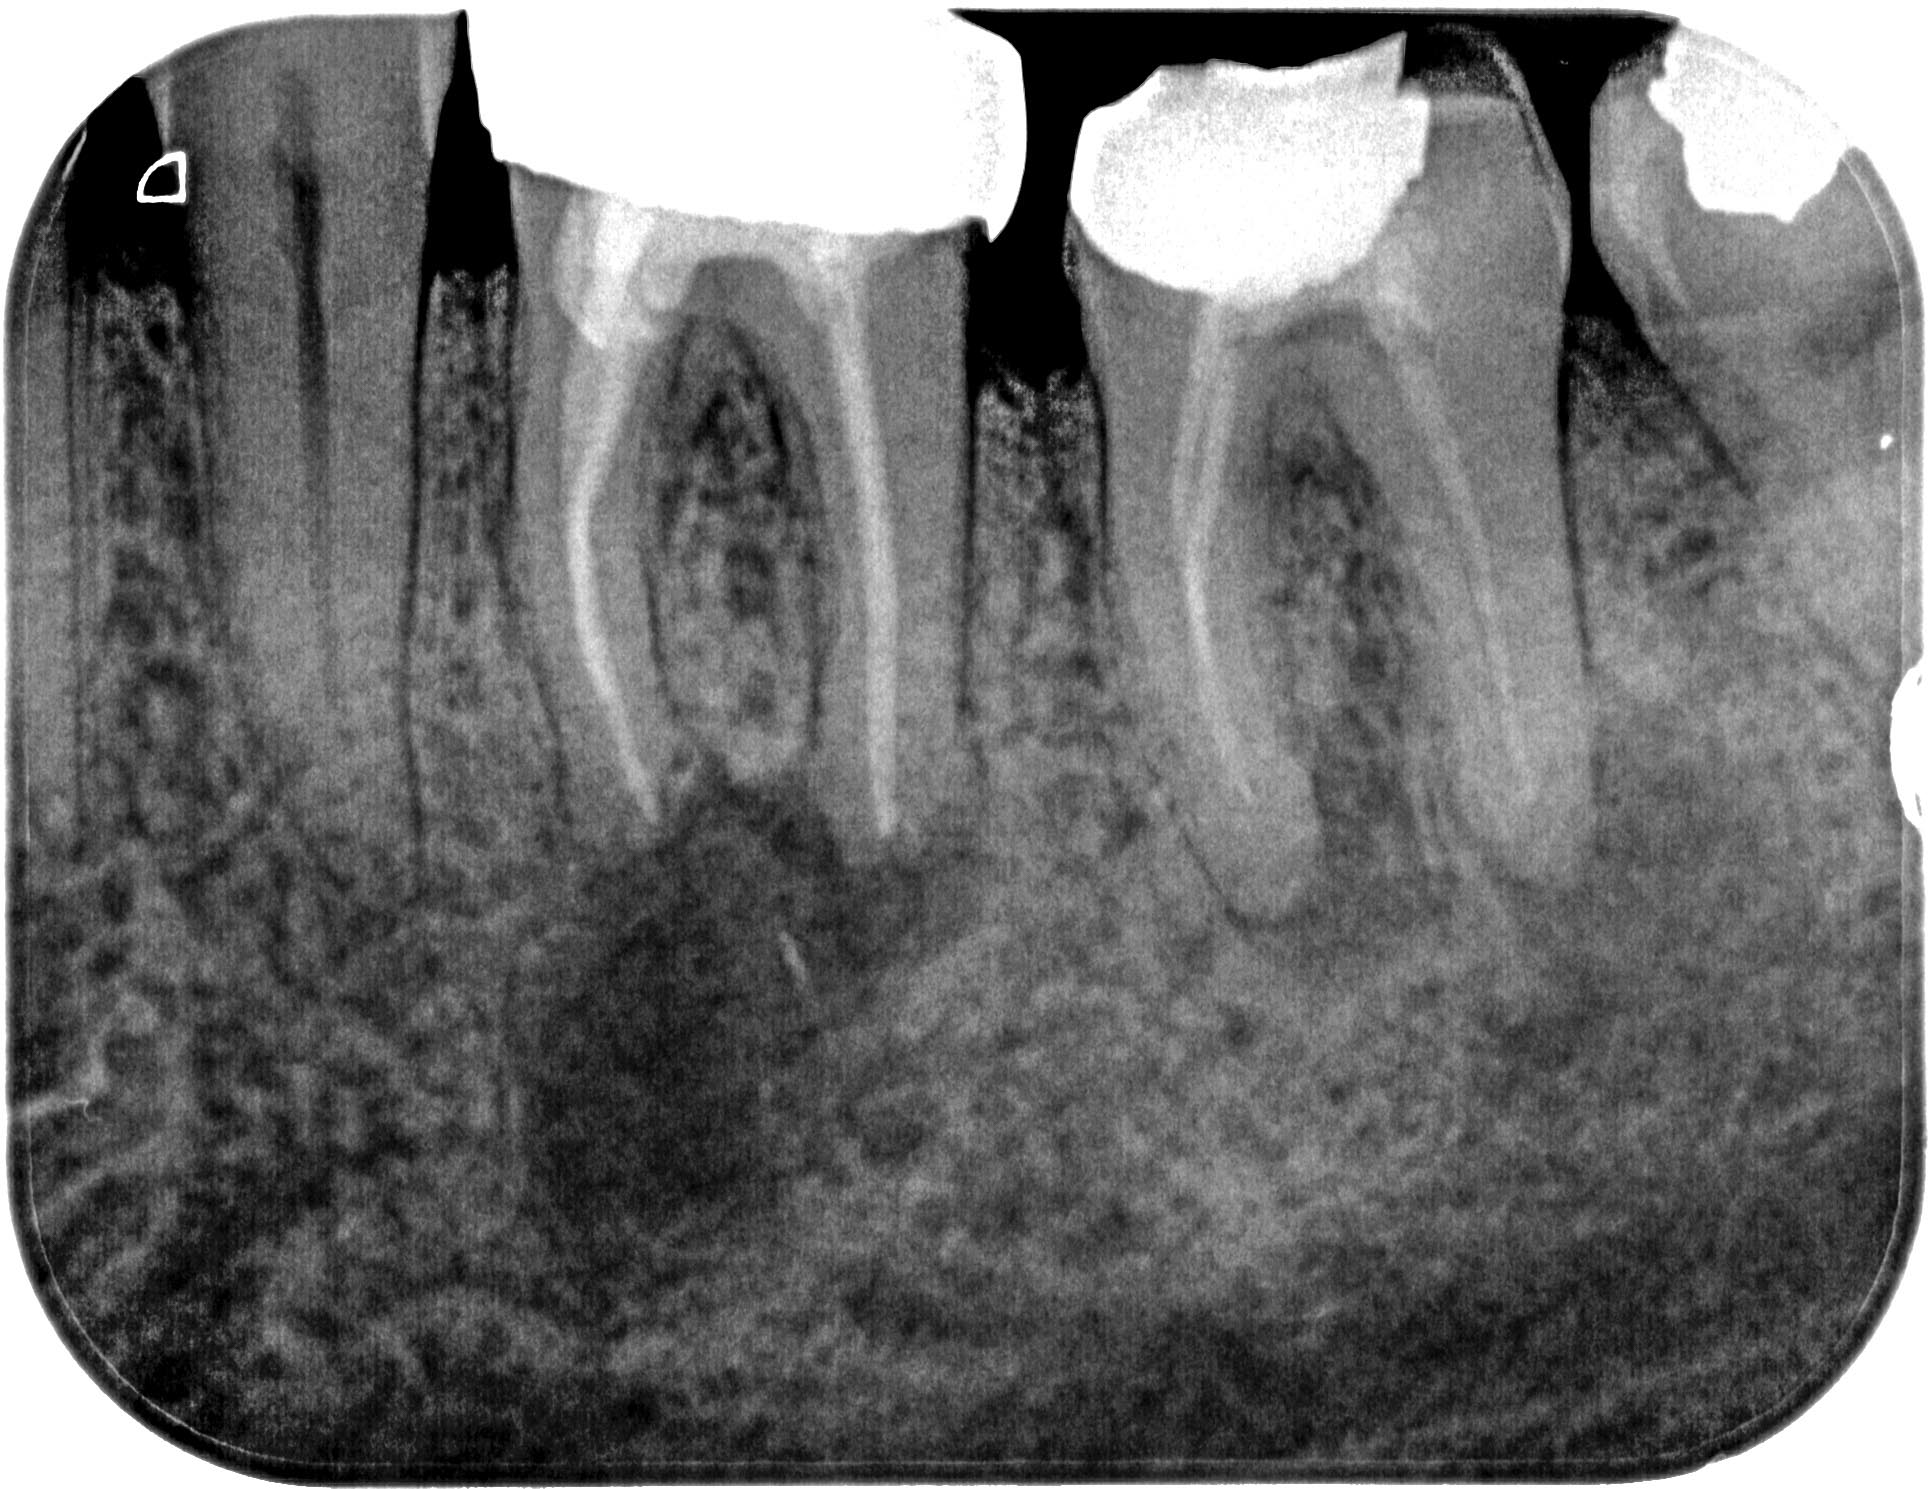

mt3637-1

1931 × 1489

3 Haselnüsse (1)

01.12.2014